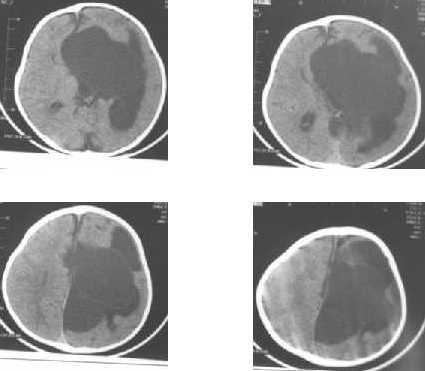

Schizencephaly and porencephaly : porencephaly